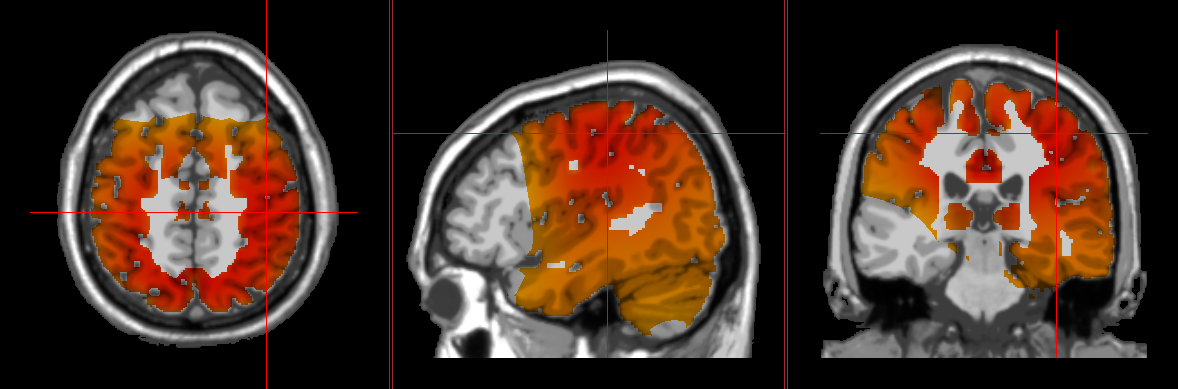

Pain is more than just a sensory experience; rather, it is a complex phenomenon involving three components: the direct sensory component, the immediate emotional experience, and the long-term emotional implications. Each of these components is mediated by a different neural pathway. In cases of chronic pain, these pathways can become overly sensitized, resulting in a reduced pain threshold and exacerbation of symptoms. In such cases, it is no longer just the bodily source of the pain that is causing our experience but rather the feedback loop between our brain and body.

Fortunately, there is hope! Studies have shown that interventions which address these underlying brain regions can have a significant impact on an individual’s experience of the pain, even if the bodily source of the pain remains unchanged! Research has shown that neurofeedback, neurostimulation, and peripheral biofeedback can all be effective for alleviating chronic pain, improving coping abilities, reducing secondary consequences, and enhancing quality of life.